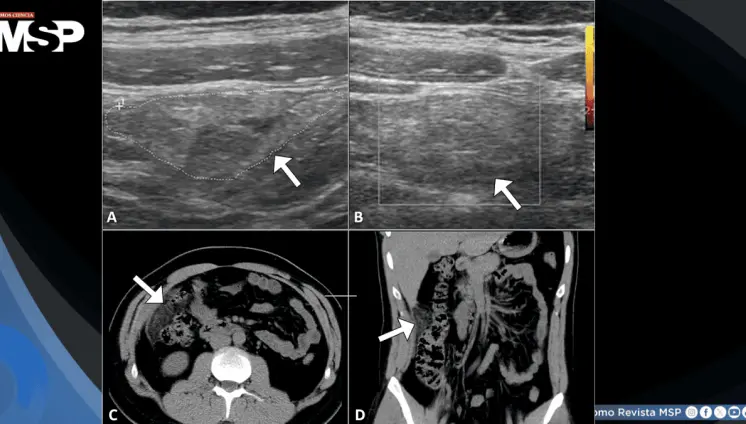

El caso destaca la importancia del reconocimiento temprano mediante tomografía computarizada y el manejo agresivo con drenaje percutáneo y antibioticoterapia de amplio espectro.